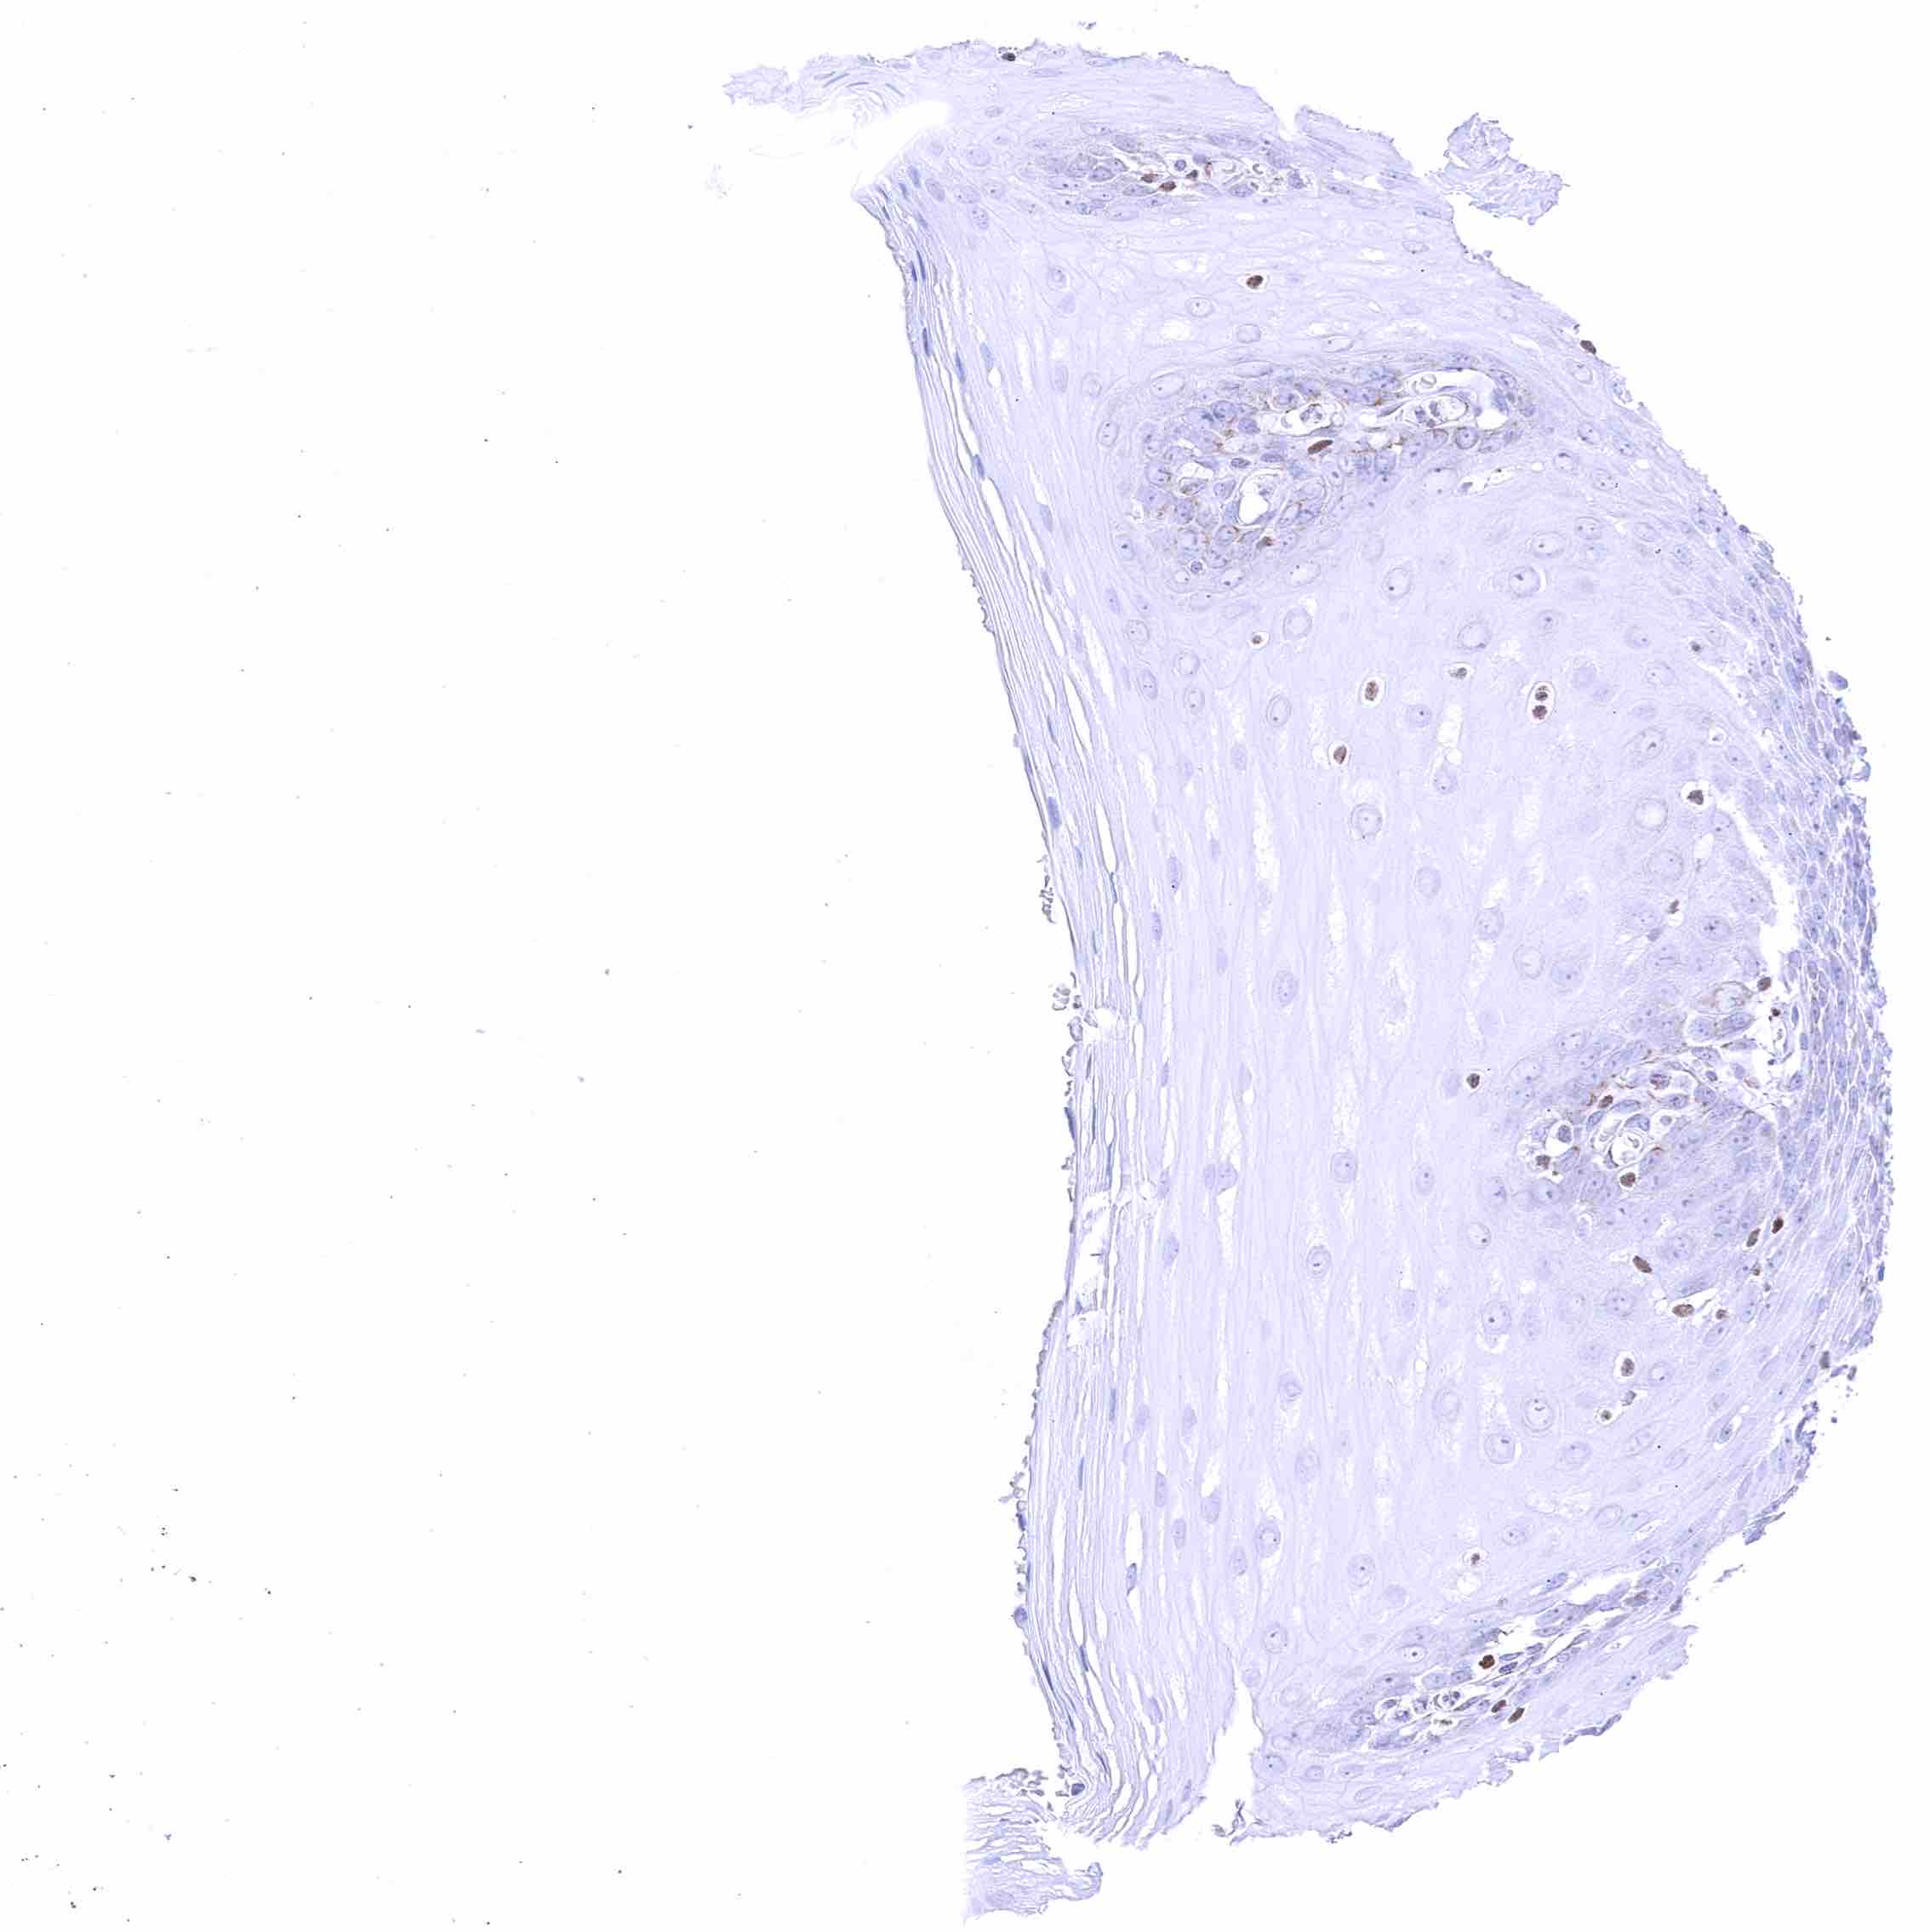

Esophagus, squamous epithelium – Weak nuclear GATA3 positivity of few lymphocytes.

Skin, anal canal – Weak to moderate nuclear GATA3 staining of squamous epithelial cells. The staining predominates in the lower half of the epidermis.

Skin, hair follicel and sebaceous glands – Strong nuclear GATA3 staining of squamous epithelial cells, cells of hair follicles, and peripheral germinative cells of sebaceous glands. Nuclear GATA3 staining is faint or absent in cells of sebaceous glands.

Uterus, ectocervix – Weak to moderate nuclear GATA3 staining of squamous epithelial cells.